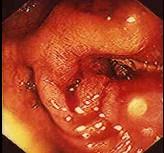

问题 女性,50岁,反复腹泻,黏液脓血便10年,加剧2月;近来明显消瘦;既往呈确诊为溃疡性结肠炎。现服用柳氮磺胺吡啶症状无缓解,肠镜检查如图,首选治疗措施为 ( )

选项 A.口服氟哌酸 B.柳氮磺胺吡啶 C.静脉滴注氢化可的松 D.口服异烟肼、利福平 E.手术治疗

答案 E